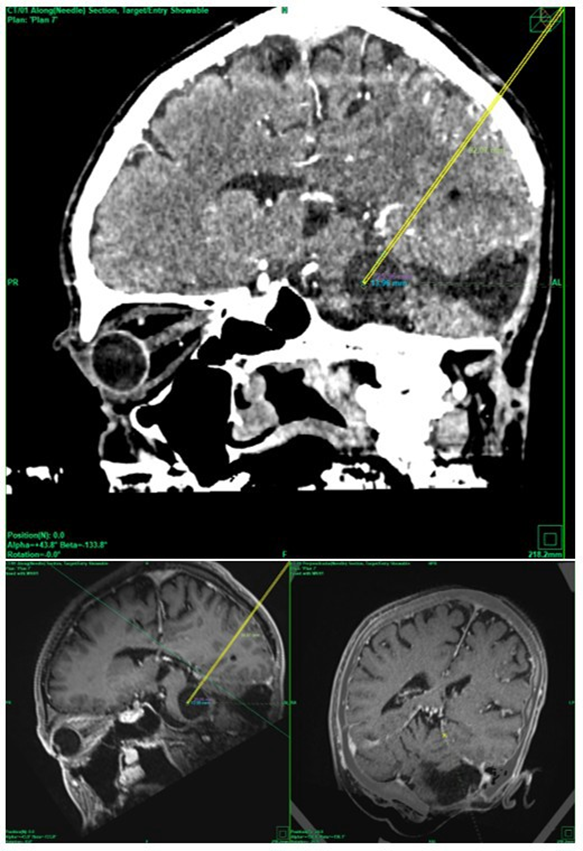

The patient was offered the alternative treatment of open fenestration and was informed that there was little to no experience regarding the outcome of this new procedure. Informed consent was obtained. On the day of the procedure, the patients received total intravenous anesthesia and a single shot of 1.5 g cefuroxime. The patient’s head was fixed in a aluminum ring (Precisis AG, Heidelberg, Germany) within a prone position. MR images with 2mm slices and a stereotactic CT were uploaded into the inomed iPS 6.0 software (inomed, Emmendingen, Germany). Several potential trajectories were evaluated to determine the safest surgical approach. A parietal transtentorial route was ultimately selected (Figure 4).

Figure 4 Stereotactic parietal transtentorial approach within the stereotactic CT scan (top) and within the MRI (bottom).

Stereotactic coordinates were established using a Riechert–Mundinger frame (Precisis AG, Heidelberg, Germany) and verified with a stereotactic phantom (Precisis AG, Heidelberg, Germany). The distance from the skull to the tentorium was measured, and a Backlund biopsy needle was advanced along this trajectory.